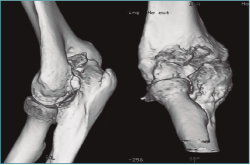

Las pruebas de imagen más útiles en este contexto son la radiografía simple (Figura 3) y la tomografía computarizada (TC) (Figuras 4 y 5), que evalúan la congruencia de las superficies articulares, la presencia de osteofitos u osificación ectópica, o alteraciones de la alineación ósea. Además, se evaluará la consolidación de fracturas previas, si es el caso, o la posible implicación del material de osteosíntesis en la falta de movilidad (si está correctamente situado, no tiene por qué interferir con la movilidad del codo)(6).

Figura 4. Artrosis de codo con formación osteofítica exuberante y fibrosis capsular, sin alteración del espacio o alineación articular, como ejemplo de rigidez extrínseca.

Figura 5. Reconstrucción sagital y tridimensional de una malunión de húmero distal, con alteración de la alineación de la superficie articular en extensión y malrotación interna, que condiciona una pérdida de flexión, como ejemplo de rigidez intrínseca.